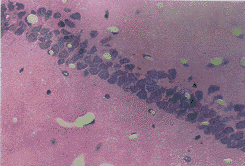

图1 正常对照组海马 CA1区锥体细胞排列整齐而致密 HE×132

图2 假手术7天组海马CA1区锥体细胞数目和形态同正常组 HE×132

图3 VD模型7天组海马CA区锥体细胞排列紊乱,脱失严重,胞核浓染 HE×132

图4 中药防治7天组海马CA1神经元排列较规则,细胞较规则,细胞轻度脱失,部分胞染变深 HE×132